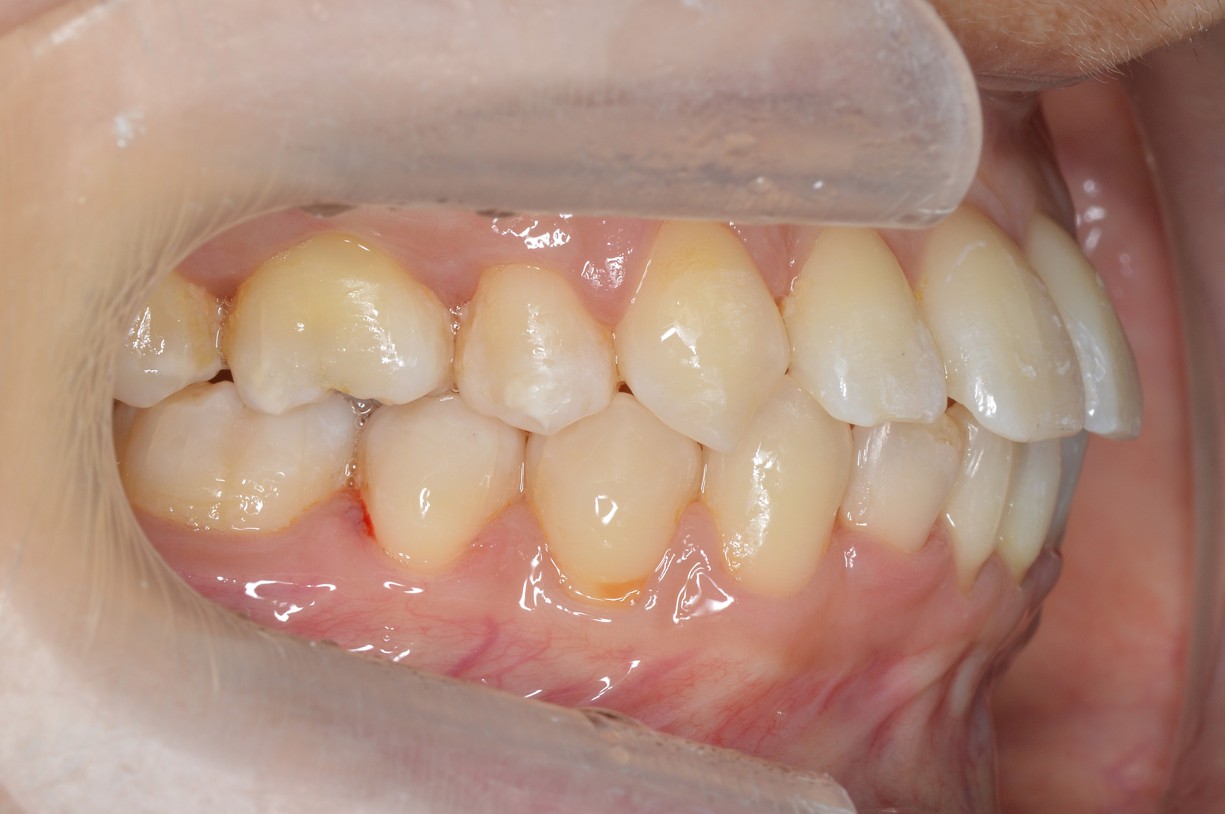

症例2

| 項目 | 詳細 |

|---|---|

| 患者様データ | 30代 女性 |

| 来院時の主訴 | 「右上の、内側に生えている歯が邪魔。」 |

| 矯正法 | 上の歯2本、下の歯2本、親知らず3本を抜歯しての矯正 |

| 通院期間 | 3年6ヶ月 |

| 治療費 | 総額:1,230,000円(税抜) 【内訳】 精密検査50,000円、メタルワイヤー矯正800,000円、月に1度の調整料5,000円、後戻り防止のリテーナー35,000円×2 |

| リスクと副作用 |

①歯を動かす事による痛みがあります。また、装置に慣れるまでは、口内炎ができやすいです。 ②歯肉が退縮するリスクがあります。装置が全ての歯に付くので、ハミガキが難しくなります。 ③長期的なメインテナンスが必要 |

| ここがこだわりのポイント!☝ | こちらの患者様は上の歯が1本内側に生えていましたが、奥歯の噛み合わせの方が問題でした。ハサミ状咬合といい、奥歯が極端に外側に向いており、下の歯と噛み合っていない状態でした。ハサミ状咬合は長期的にみると、前歯に大きな負担がかかったり、磨きにくい事による虫歯や歯周病になりやすいなどのリスクがあります。治療期間はかかりましたが、見た目の良さだけでなく、機能的にも改善しました。 |